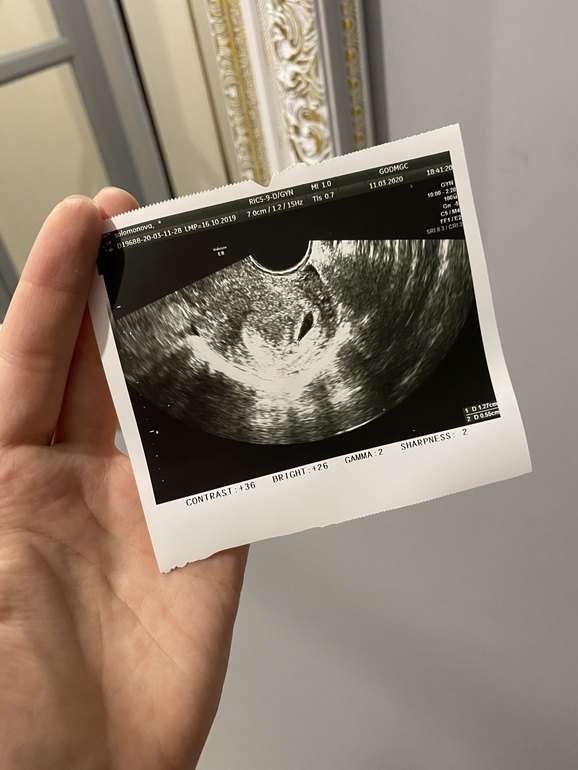

Результаты: УЗИ, КТГ, доплера, скринингаМесячные были 28 января, но овуляция была поздняя. По узи поставили 4 недели эмбриональные (это от овуляции), а по графику примерно 3 нед 3 дня (5 недель и 3 дня акушерских)

В матке плодное яйцо 12х5,5х11мм, желточный мешок 3. Врач сказала, что все хорошо.

Но я же влезла в интернеты и посмотрела таблицы. Типо в 4 эмбриональные недели плодное яйцо должно быть 18мм. У кого какие размеры пя были в 5-6 акушерских недель?